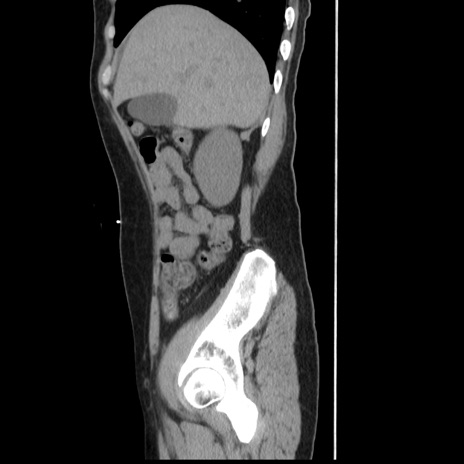

冠状断像